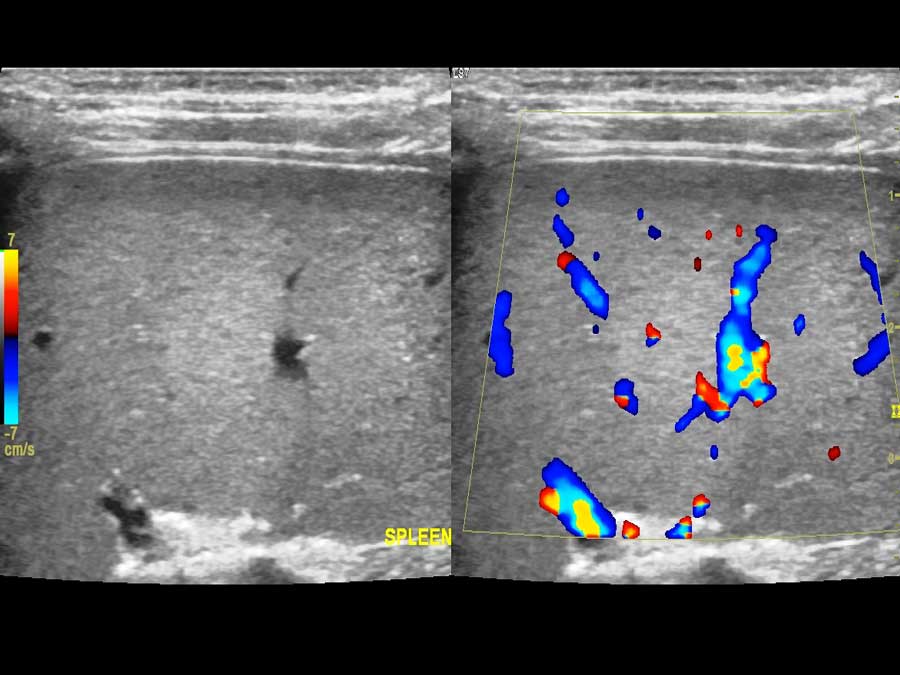

- Triplex κοιλιακής αορτής, λαγονίων αρτηριών, νεφρικών αρτηριών, σπληνοπυλαίου άξονα, σύνδρομο καρυοθραύστη

- Τriplex κοιλιακής αορτής, λαγονίων αρτηριών και φλεβών, νεφρικών αρτηριών, σπληνοπυλαίου άξονα